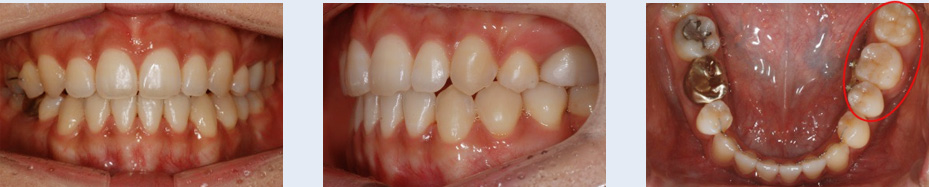

2년 전 식립한 임플란트의 보철물이 탈락된 상태로 1년간 지내오신 25세 여성입니다. 임플란트 식립을 위해

사용한 인공 뿌리를 제거하고 치아가 가지런해 지길 원하셨습니다. 자연치아로만 치료를 진행할 수 있도록 하기

위해 인공 뿌리를 제거하고, 빈 공간으로 치아를 이동시켰습니다.

임플란트 제거 후 생긴 빈 공간으로 브라켓을 부착한 사랑니를 이동시켜 추가적인 임플란트 식립이나 보철 치료

없이도 자연스러운 치열을 갖게 되었습니다.